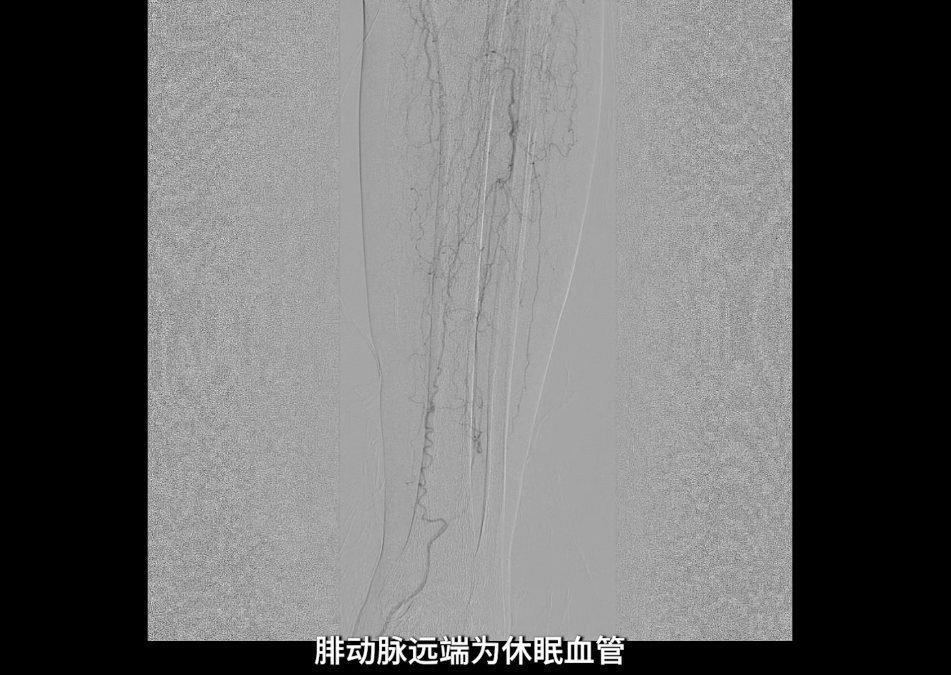

膝下动脉三支主干均闭塞,胫后动脉远端经侧支循环显影;腓动脉远端为“休眠血管”,通过与胫后动脉的交通支实现逆向显影。